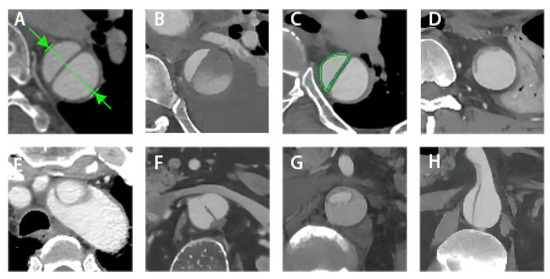

| Partial thrombosis of FL, n (%) | 9 (60.0) | 7 (8.6) | <0.001 |